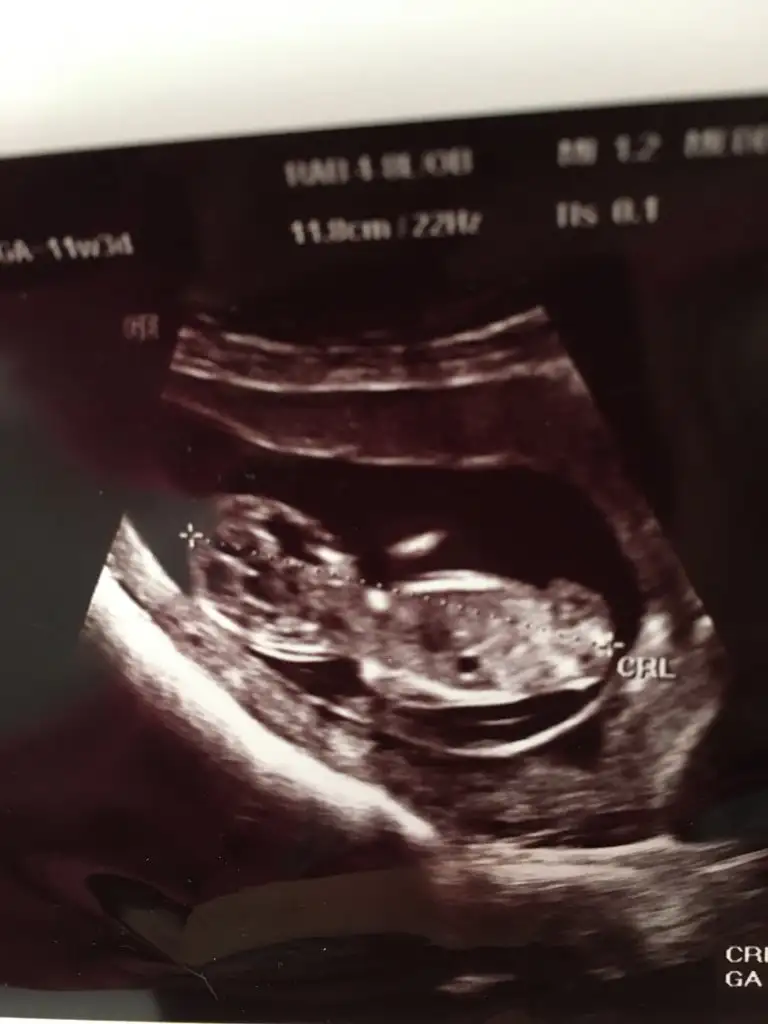

Selamlar, bu USG de benim minigime ait yorumlarsanız sevinirim

Kız gibi sanki tam net değil nubu başka usg de paylaşın